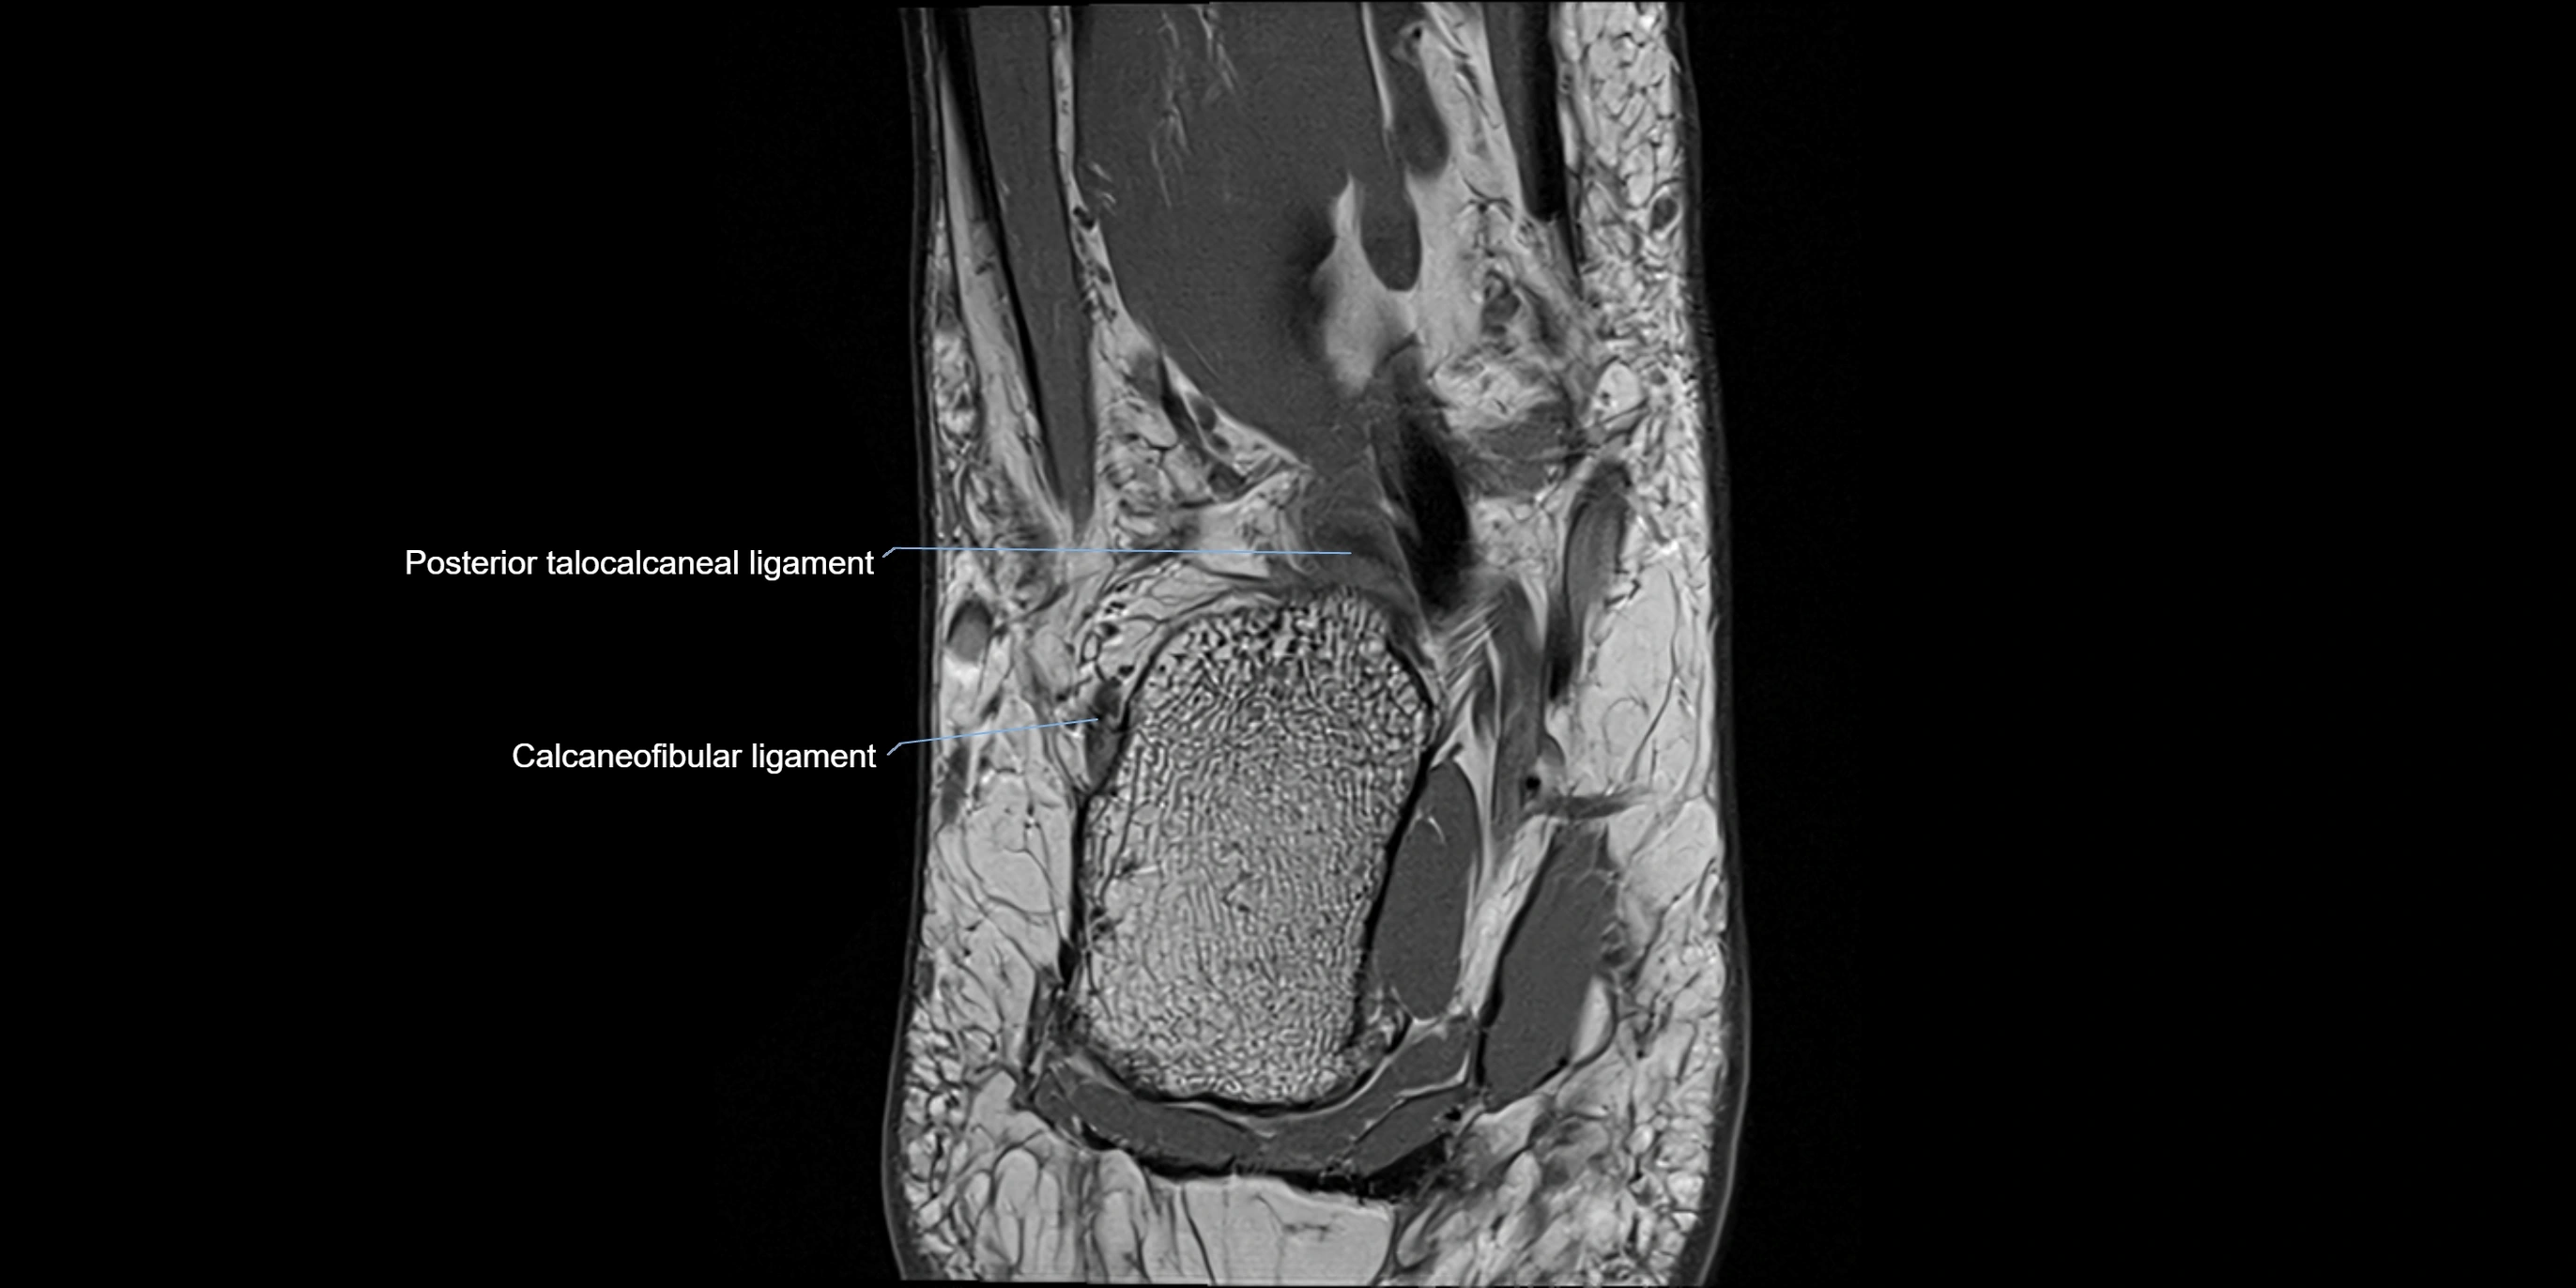

MRI image

image